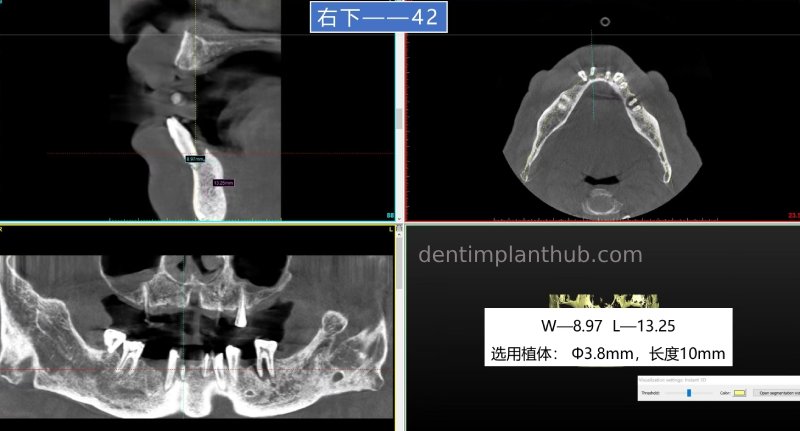

42, 32, immediate extraction and implantation, follow-up restoration together with continuous crowns;

42, ready-to-use implant, implant model 3810;